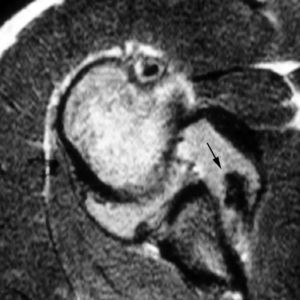

Rotura simple del labio glenoideo posterior

Esta lesión se produce a consecuencia de una dislocación posterior y puede acompañarse de una fractura por impactación de la parte anterior de la cabeza humeral (Hill Sachs invertido) (fig. 13).

Fig. 13.--Rotura del labio glenoideo posterior. Artrorresonancia axial T1 con supresión grasa que revela una rotura del labio glenoideo posterior (flecha).